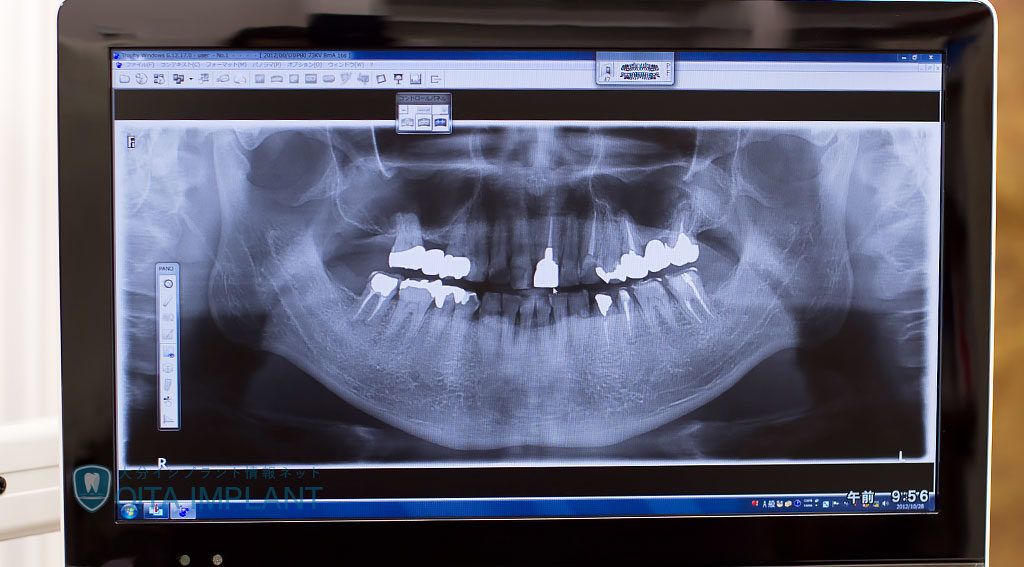

お口の病気とケア レントゲン 歯科放射線について(X線) 2019年8月31日 歯科医院では、レントゲンや撮影でのX線検査により、隠れた虫歯や細くて複雑に分岐した根管、歯槽骨の減り具合や骨密度、歯茎の奥に溜まった歯石だけでなく歯や歯の周り、顎の骨格まで総合的に把握することができます。しかしその場合、X線検査による被爆が気になる方も多いのではないでしょうか。医院によっては、問診票にレントゲン撮影を希... oita-implant